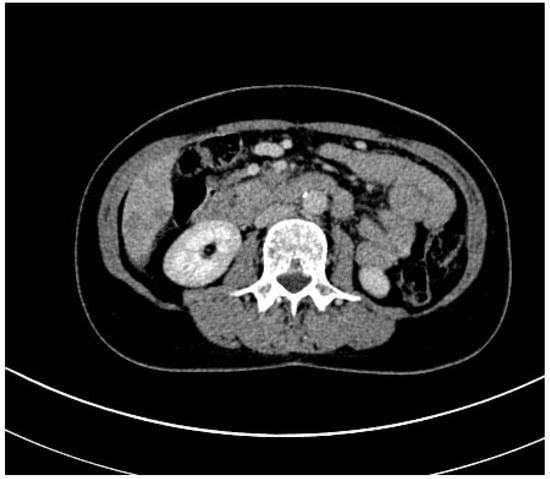

3.1. Computed Tomography

- Albano, D.; Messina, C.; Vitale, J.; Sconfienza, L.M. Imaging of sarcopenia: Old evidence and new insights. Eur. Radiol. 2020, 30, 2199–2208. [Google Scholar] [CrossRef]